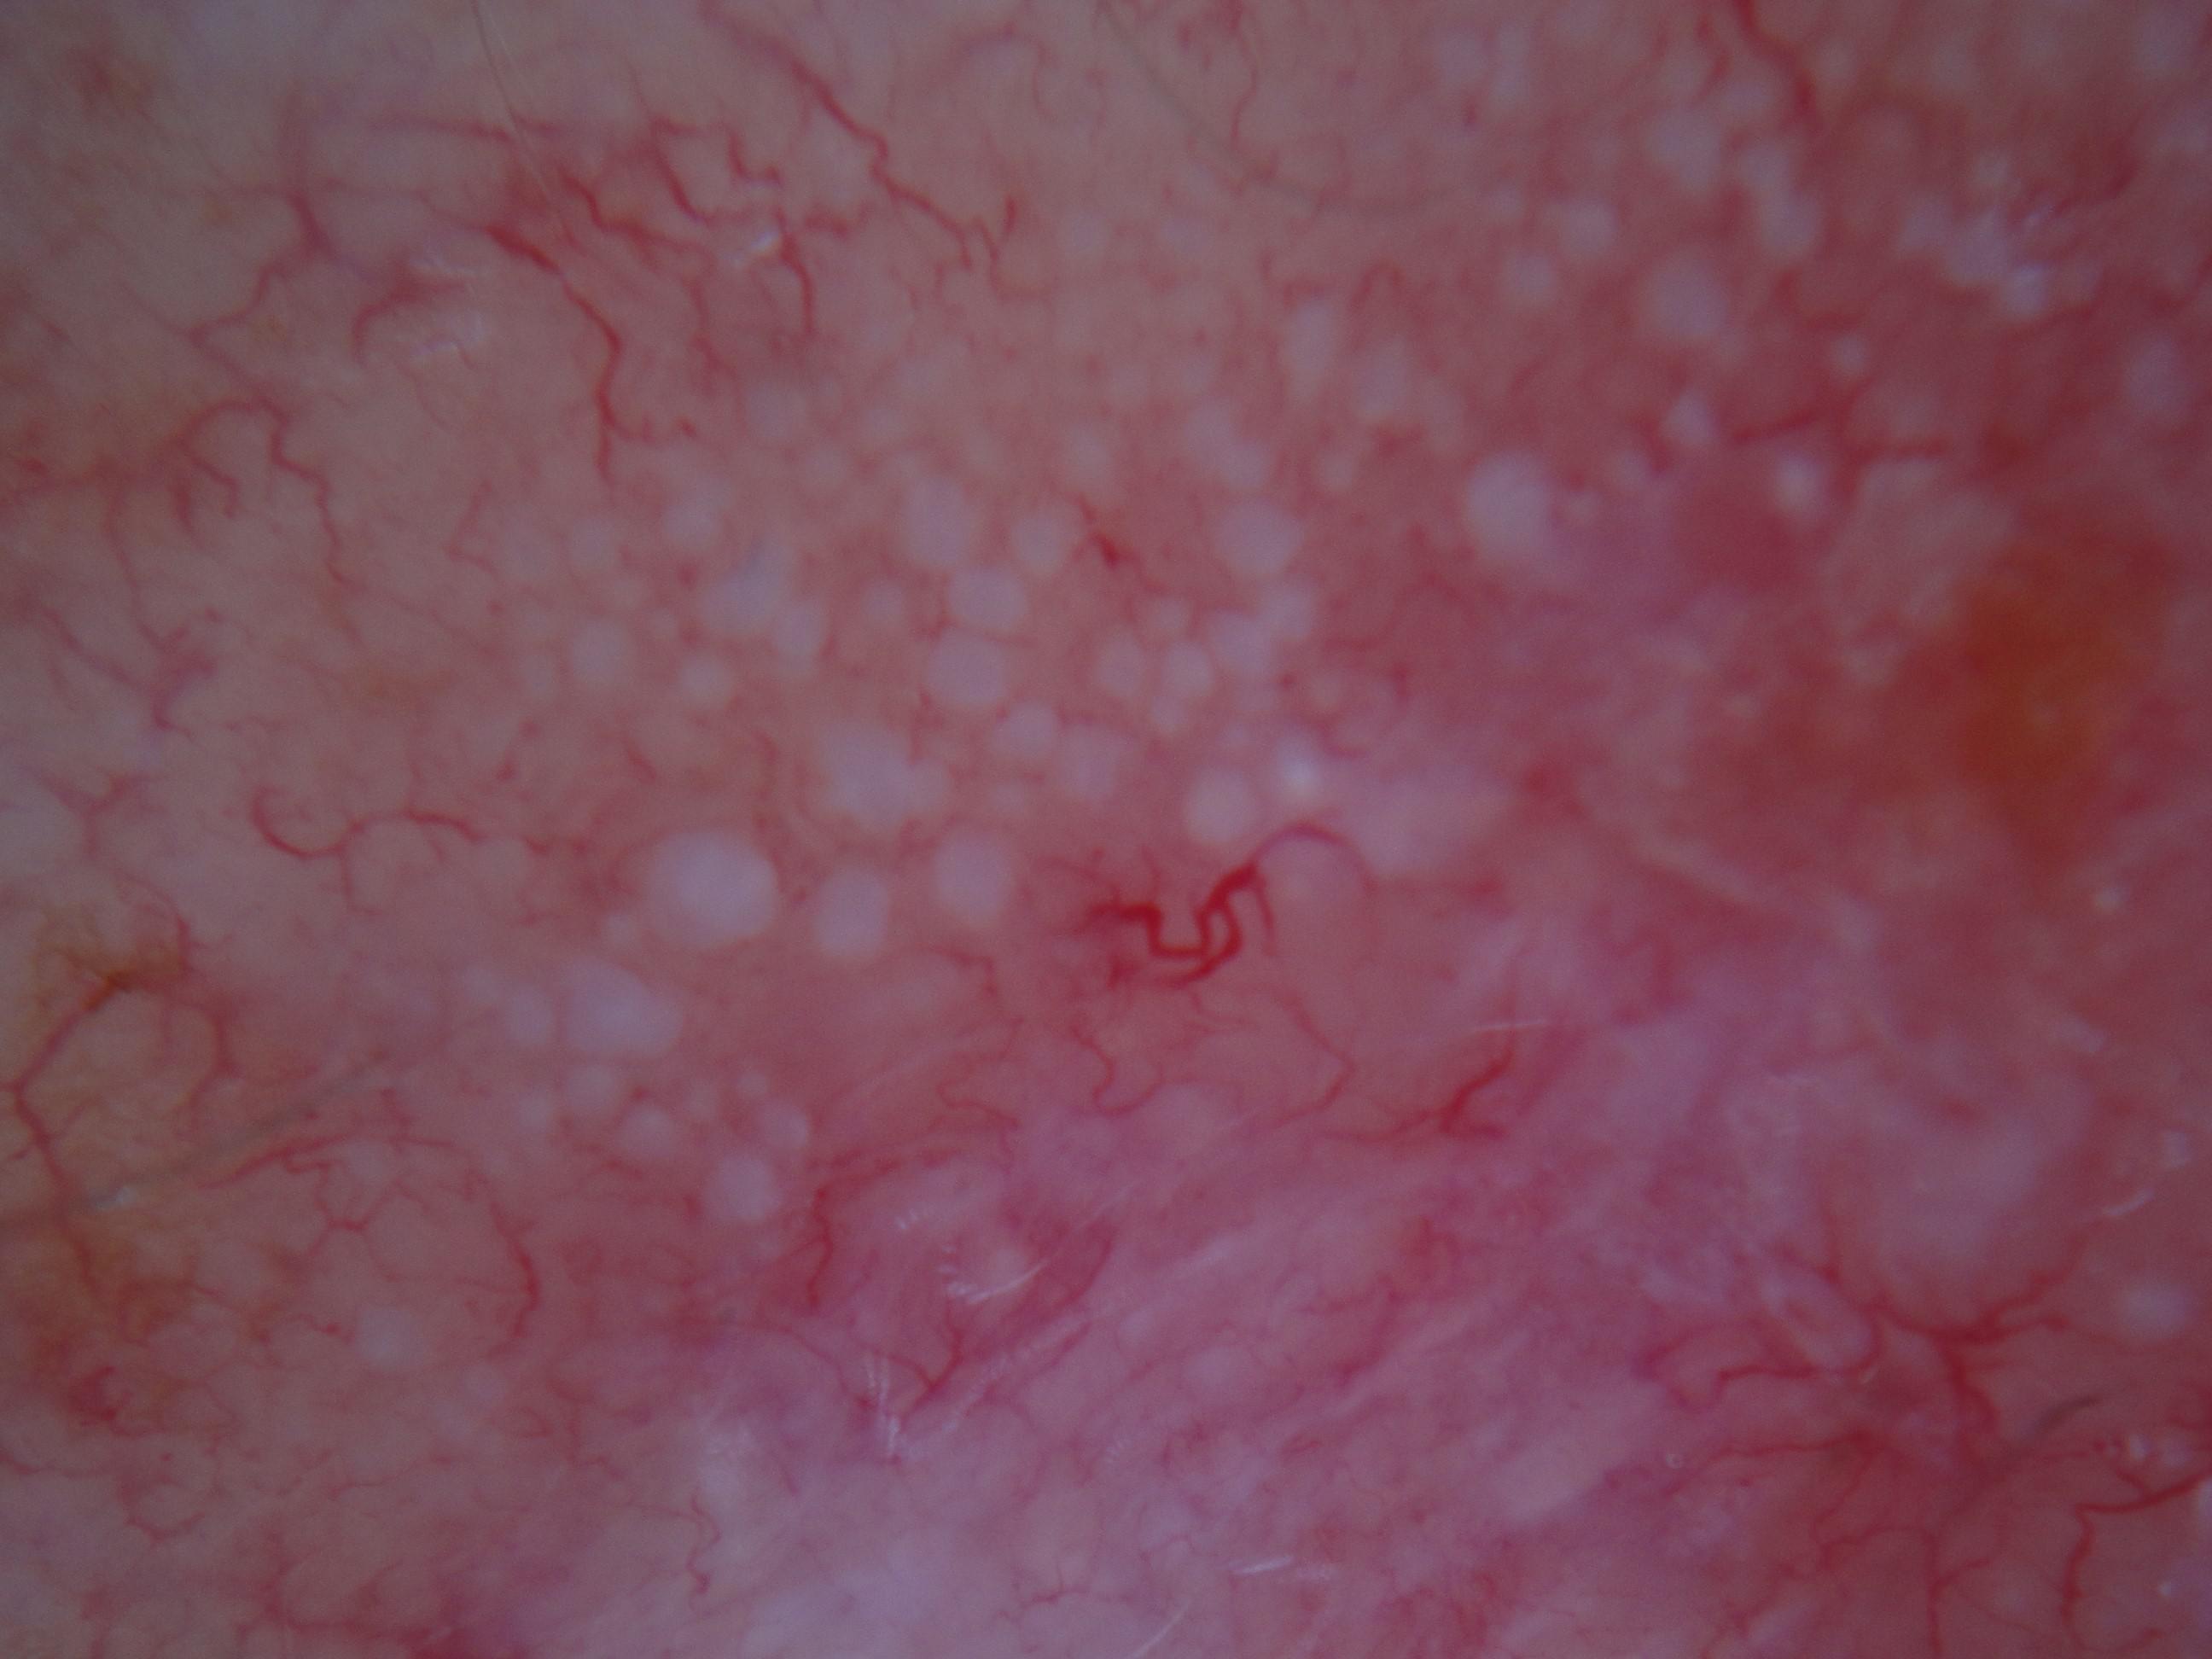

Biopsy-confirmed melanocytic and non-melanocytic skin lesions. This dataset includes over 500 melanomas. Many images have polarized and contact variants.